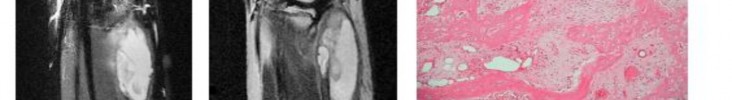

A 15-year-old male presents with deep knee pain awakening him at night. Radiographs show a permeative destructive lesion in the distal femoral metaphysis with a 'sunburst' periosteal reaction and Codman's triangle.

Biopsy confirms high-grade conventional osteosarcoma. What is the most critical prognostic factor for long-term overall survival in this patient?

Explanation

For localized high-grade osteosarcoma, the most important prognostic indicator is the histologic response to neoadjuvant chemotherapy. This is evaluated during the definitive resection. A 'good response' is typically defined as greater than 90% or 99% tumor necrosis. Patients who achieve this level of necrosis have a significantly improved disease-free and overall survival rate compared to 'poor responders' who have extensive viable tumor cells remaining.